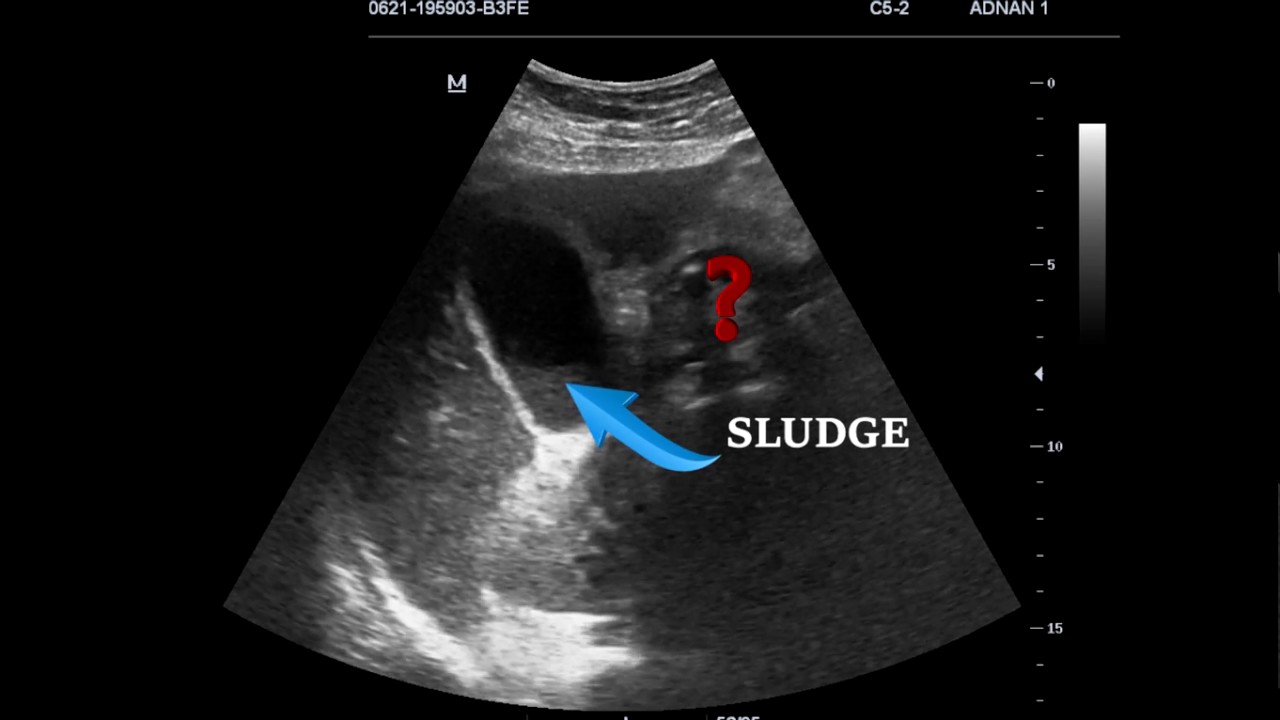

From www.youtube.com

EMERGENCY ULTRASOUND IN RIGHT UPPER QUADRANT PAIN; CASE 1 YouTube Cholestasis Upper-Right Quadrant Pain Findings that suggest a cause outside the liver include certain kinds of abdominal pain (such as intermittent pain in the upper right side of the abdomen and sometimes also in the right. A minority of patients experience pain in the area of the liver, under the right ribs 4. Intrahepatic cholestasis of pregnancy (icp) is a liver disorder in the. Cholestasis Upper-Right Quadrant Pain.